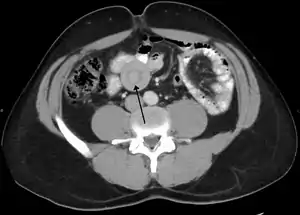

| An intussuception as seen on CT | |

An intussusception is often suspected based on history and physical exam, including observation of Dance's sign. A digital rectal examination is particularly helpful in children, as part of the intussusceptum may be felt by the finger. A definite diagnosis often requires confirmation by diagnostic imaging modalities. Ultrasound is the imaging modality of choice for diagnosis and exclusion of intussusception, due to its high accuracy and lack of radiation. The appearance of target sign (also called "doughnut sign" on a sonograph, usually around 3 cm in diameter, confirms the diagnosis. The image seen on transverse sonography or computed tomography is that of a doughnut shape, created by the hyperechoic central core of bowel and mesentery surrounded by the hypoechoic outer edematous bowel.[10] In longitudinal imaging, intussusception resembles a sandwich.[10] It is also called "pseudokidney" sign because hyperechoic tubular centre is covered by a hypoechoic rim producing a kidney-like appearance.[11]